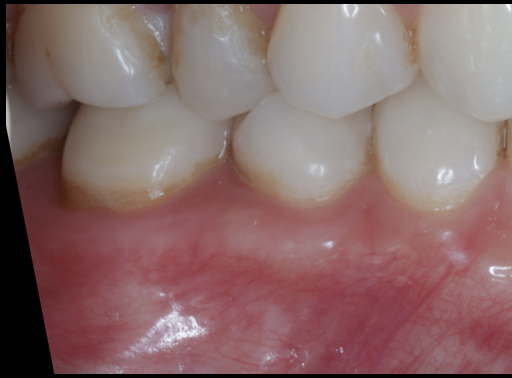

上唇の腫脹を認め、CT検査にて根尖部に嚢胞様透過像を認めた。左上の前歯が不自然に大きく噛み合わせが強くなっていたことがフレアアップの一因と考える。精密根管治療を行い、感染経路を遮断したのち歯根端切除術にて嚢胞を摘出した。

治療中